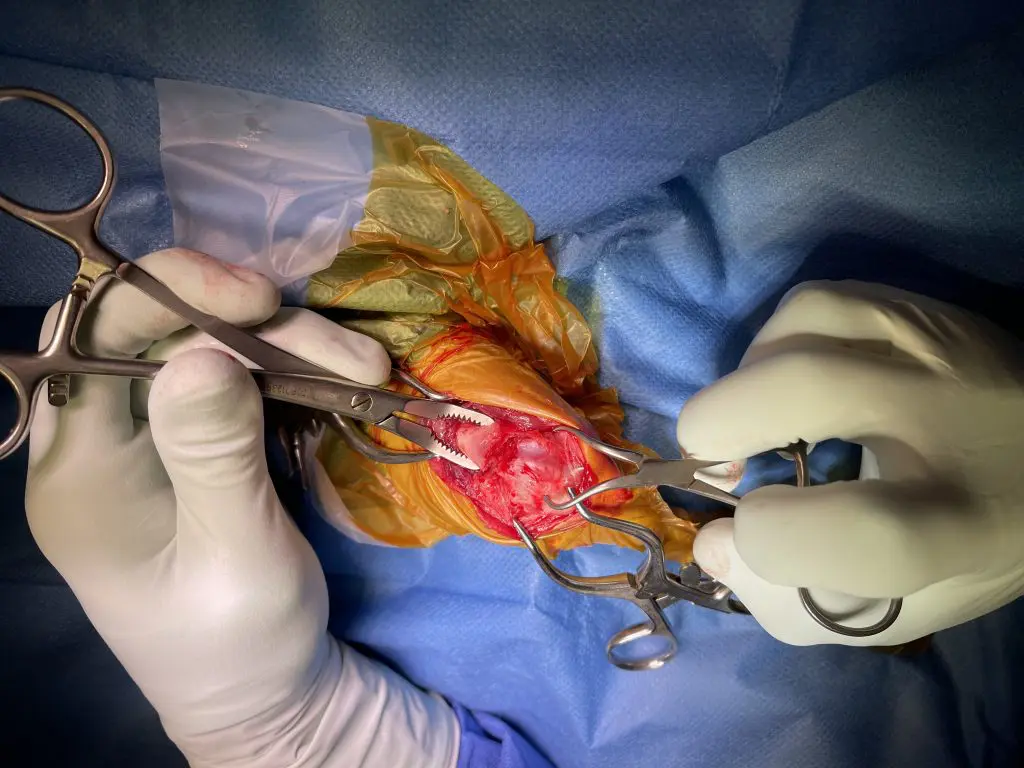

Dado el tipo de fractura y el estado de Pitu, optamos por un tratamiento quirúrgico que permitiera una correcta estabilización y una recuperación funcional del miembro afectado. Realizamos un abordaje lateral al foco de fractura y, una vez expuestos los fragmentos óseos, procedimos a su reducción.

Para mantener los fragmentos en su posición correcta de forma temporal, utilizamos una aguja de Kirschner de 1,2 mm. Posteriormente, realizamos la fijación definitiva mediante una placa de titanio y bloqueo condilar de 2 mm, un implante especialmente indicado para estos casos en animales de pequeño tamaño.